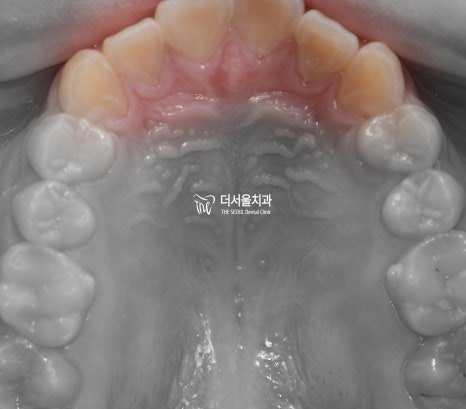

왜소치 란[Peg lateralis] 정상적인 크기보다 작은 것을 말합니다. 물론, 단어만 들었을 때 생소하게 느껴질 수 있으나 체구가 작은

치아 삐뚤거림, 총생, Crowding 이 있는경우 어떻게 개선하나요?

총생은 턱의 크기에 비해서 치아 크기가 크고 치열이 맞지 않아서 서로 겹쳐 있는 상태를 말합니다. 흔히 말하는 덧니도, 총생의 […]